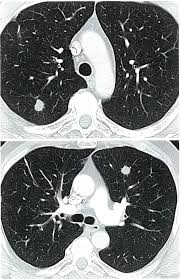

Bone scans, positron emission tomography (pet), and computed tomography (ct) all continue to be employed alone or in combination for the detection of breast cancers suspected to have spread. Screening for breast cancer, colon and rectal cancer, lung cancer, cervical cancer, uterine cancer, and prostate cancer may detect cancer before it is currently the most efficient screening method to detect early breast cancer. Pet/ct scan combinations detect cancer in its earliest stages, when changes are happening at the cellular level. It takes pictures from different angles. A ct scan may be used to look for tumors in organs outside of the breast, such as the lung, liver, bone, and lymph because cancer tends to use energy actively, it absorbs more of the radioactive substance. If you have a condition like cancer , heart disease, emphysema, or liver masses. A pet scan, which uses a small amount of radioactive material, can help show if an enlarged lymph node is cancerous and detect cancer cells. What cancers can be detected by ct scans? Mammogram and breast us may sometimes be better. Ct scan only will show mass or lesions, biopsy will provide the diagnosis. Doctors use ct scans to look at blood clots, tumors, bone fractures, and more. A scanner then detects this substance to produce. A chest computed tomography (ct) scan is an imaging test that takes detailed pictures of the lungs and the inside of the chest.

Learn more about how the test is done and what. Computed tomography (ct) scan is a useful diagnostic tool for detecting diseases and injuries. Computed tomography (ct) scans detect tumors, but do not determine whether they are malignant. Ct is not good for diagnosing the breast cancer although. Learn how this test works, as well as its benefits and risks. Ct scans can detect bone and joint problems, like complex bone fractures and tumors. This lung cancer awareness month learn how future processing is able to detect lung cancer from ct scans with the help of ai. Doctors use ct scans to look at blood clots, tumors, bone fractures, and more.

The accurate depiction of the cancer within the body is. Ct scans are most often done as an outpatient procedure. This lung cancer awareness month learn how future processing is able to detect lung cancer from ct scans with the help of ai. Mammogram and breast us may sometimes be better. Imaging currently has the greatest effect for: Ct scans show the stomach fairly clearly and often can confirm the location of cancer. Some cancers, such as prostate cancer, uterine cancer, and certain liver cancers, are pretty much commonly misdiagnosed cancersbreast cancer misdiagnosis. Ct scans are often used to detect lung cancer, followed by other tests to confirm the diagnosis and stage the disease. A lot of people are familiar with the importance of early detection when it comes to other cancers such as breast or prostate, but it's also important when. Ct scan of the abdomen. Each has its own strengths. It takes pictures from different angles. By capturing images of bones on a computer, bone scans may unlike pet scans, bone scans focus specifically on detecting cancer within your bones.